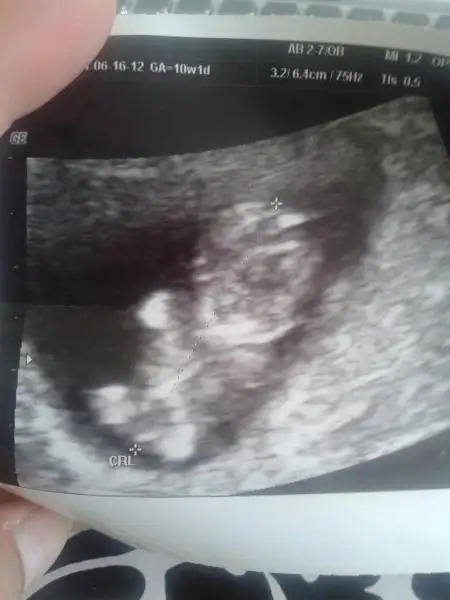

Kızlar benim bebegimede yorum yaparmısınız 11.4 haftalıkEki Görüntüle 1171730

iPhone 'den Kadınlar Kulübü aracılığı ile gönderildi